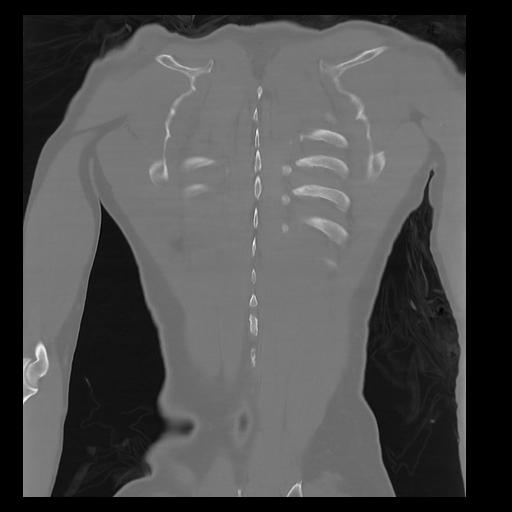

32 PULMON,CE,Coronal,3.000,PULMON,Coronal,